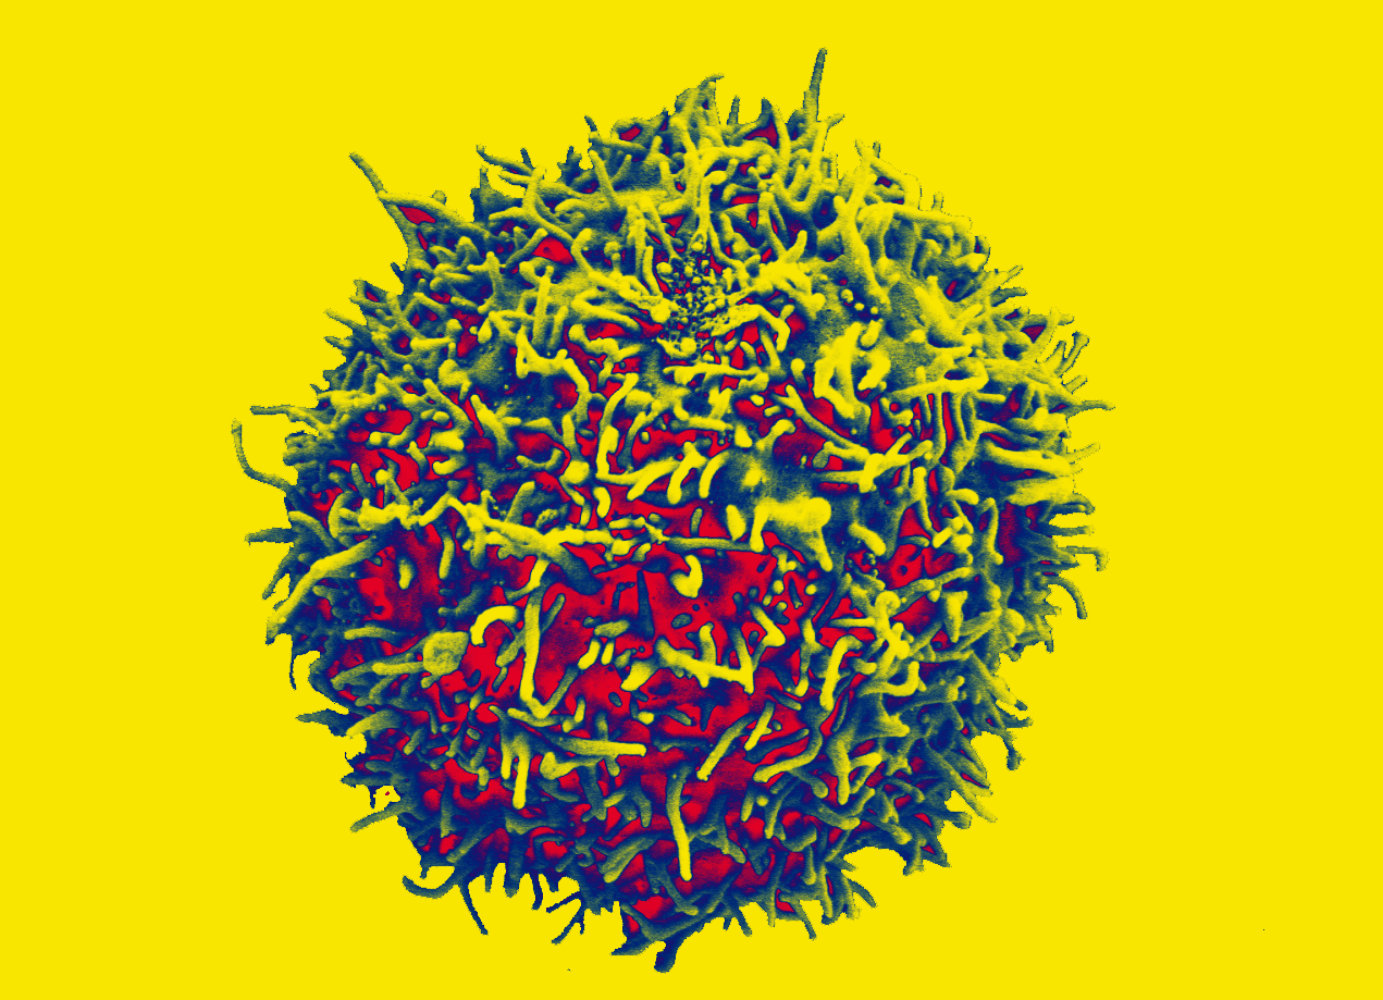

Innsbruck, am 3. Juli 2023: Vor zehn Jahren wurden die ersten Leukämiepatient:innen mit chimären Antigenrezeptor (CAR) exprimierenden T-Zellen behandelt. Ein Jahrzehnt später sind viele der Betroffenen noch immer ohne Krankheitssymptome. Im Rahmen dieser innovativen CAR-T-Zell-Therapie werden bestimmte Immunzellen, die T-Zellen, aus dem Blut der Patient:innen gewonnen und in der Folge gentechnisch aufgerüstet und den Patient:innen über eine Infusion wieder zugeführt. Die mit einem Tumorerkennungsrezeptor ausgestatteten CAR-T-Zellen sind in der Lage, Tumorzellen gezielt zu erkennen, an diese anzudocken und sie zu zerstören. Bei schwer behandelbaren soliden Krebserkrankungen wie dem nicht-kleinzelligen Lungenkarzinom (NSCLC) blieb jegliche Wirksamkeit von CAR-T-Zellen bislang jedoch aus.

Gottfried Baier, Direktor des Instituts für Zellgenetik an der Medizin Uni Innsbruck und österreichischer Pionier der Krebsimmuntherapie, ist den Ursachen der Therapieresistenz von CAR-T bei NSCLC auf der Spur. Mit seinem Team konnte er bereits mehrfach belegen, dass das intrazelluläre Protein CBLB* eine Schlüsselrolle in der Hemmung der anti-tumoralen Funktion von Immunzellen einnimmt: „Krebszellen wenden verschiedene Tricks an, um dem Immunsystem zu entkommen und das Protein CBLB* fungiert dabei als eine Art Checkpoint in der Anti-Tumor-Immunantwort. Der Tumor missbraucht sozusagen die Immunzelle und macht aus einer tumorbekämpfenden Zelle eine inaktive und für den Tumor völlig harmlose Zelle.“

Mit der Blockade von Immun-Checkpoint Molekülen in CAR-T-Zellen könnte sich nun eine vielversprechende Therapieoption eröffnen, die tumorzellschädigende Funktion der schon heute verfügbaren CAR-T Zellen am Ort des soliden Tumors entscheidend zu verbessern. Solcherart hergestellte Zellen könnten ein potenziell effektives „lebendes Medikament“ zur Abtötung von Tumorzellen auch in der immunsuppressiven Tumorumgebung darstellen. Genau diesen Weg wollen Gottfried Baier und invIOs in einem neuen, von der FFG geförderten BRIDGE*-Projekt (Extension of CD8 CAR-T cell therapy success by CBLB pathway blockade; Acronym „EXCEL-T“) beschreiten.